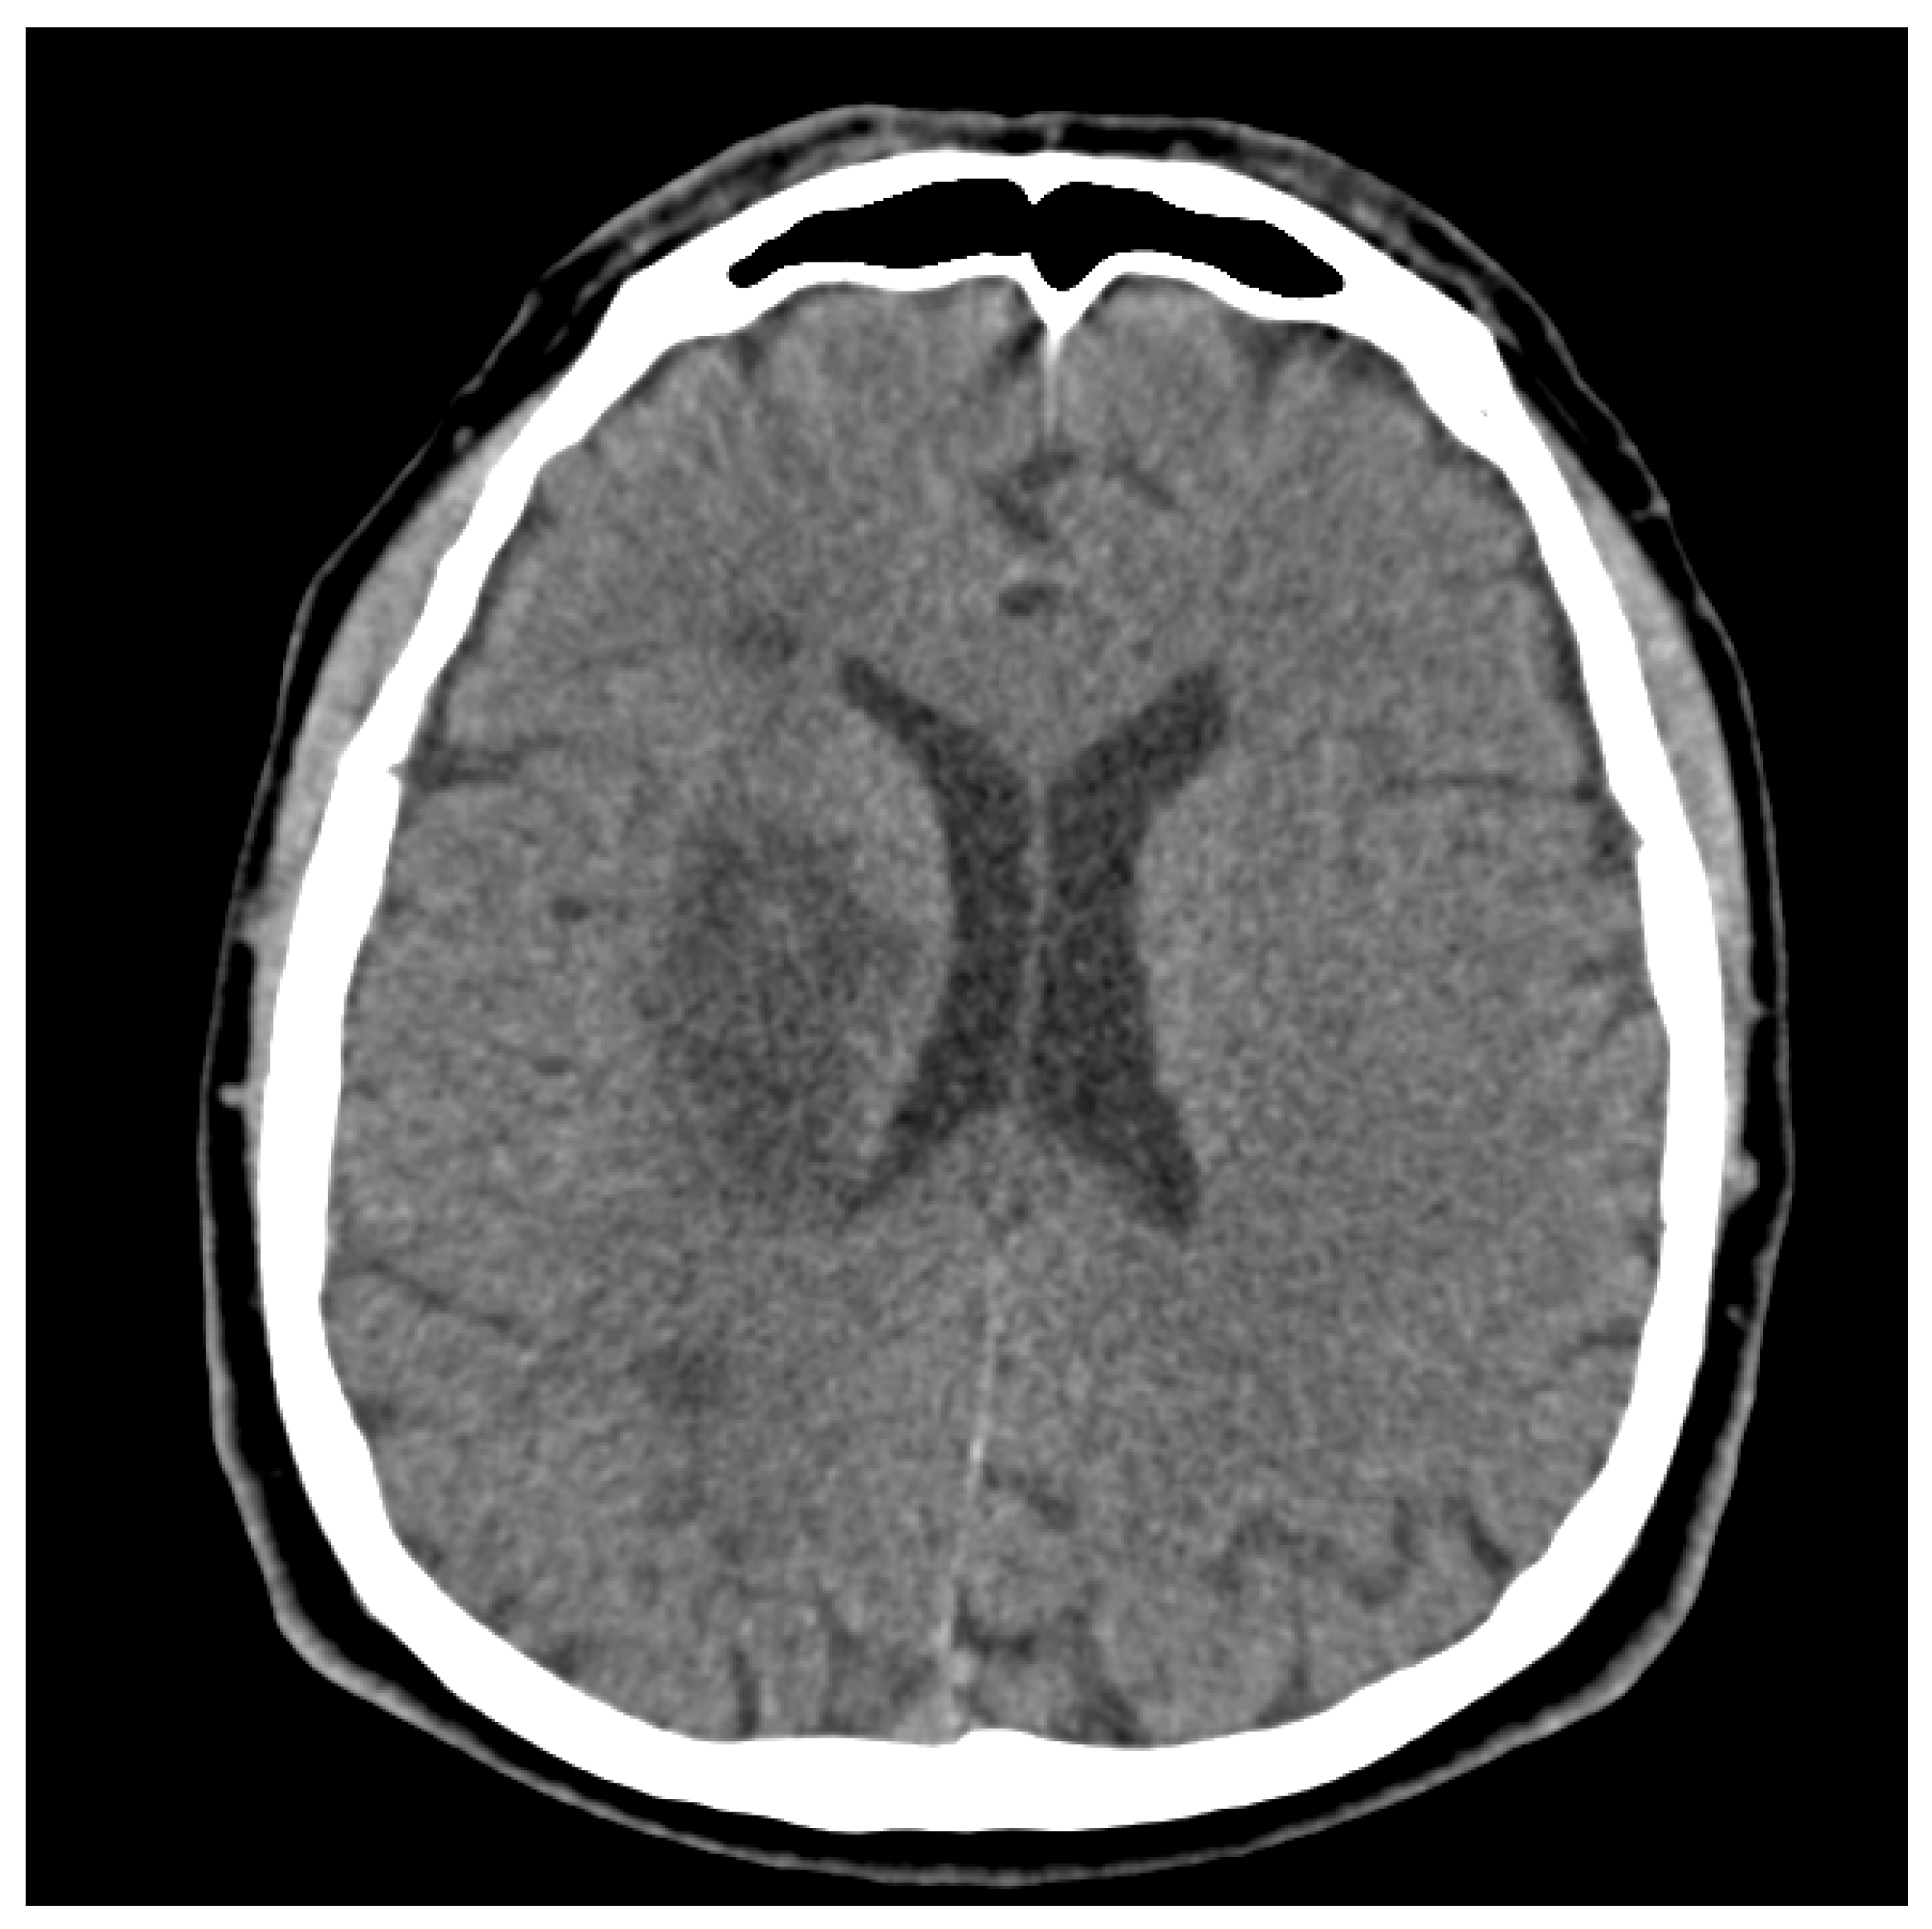

2.1. Patient Characteristics: De-Identified Patient-Specific Information

2.2. Patient Characteristics: Primary Concerns and Symptoms of the Patient

2.3. Medical, Family, and Psychosocial History, including Relevant Genetic Information